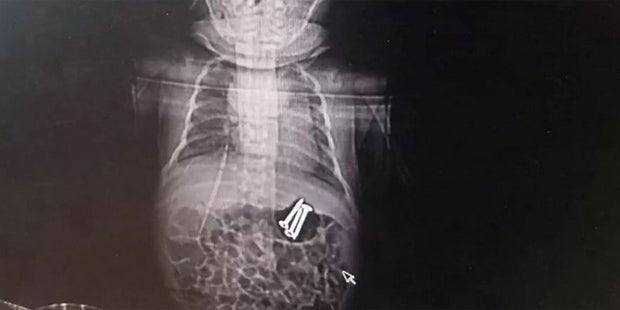

An dem Säugling wurde eine Magenspiegelung durchgeführt, mittels eines Magneten konnten die drei Schrauben aus dem Bauch entfernt werden.

"Wir mussten den 7,5-Millimeter-Magenspiegel benutzen, dabei hatten wir Angst, dass er zu dick für das Baby ist", erklärte Arzt Li Xiaoqin den gefährlichen Eingriff laut der britischen Zeitung "Metro". Es sei ein Risiko gewesen, das man aber eingegangen sei, da "es besser als eine Operation ist".